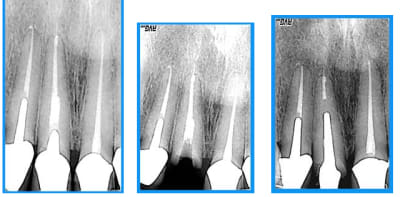

curieux de voir que le dépassement a suivi la dent... serait un instrument cassé?

Dépassement dt5hca - Eugenol

et l'interrogation de spriford? je me pose la même question.

aucune idée

je ne me suis pas acharnée à retirer le cône noyé ds la pâte(acryl? ou thermafill mais cela existait il à l'epoque?) vu l'absence d'image apicale et.... le fait que je n'y suis pas arrivée:)

oui, c'est visiblement bien toléré, juste frustrant de ne pas savoir, filet de ciment? cone? en tous cas, ça suit la dent.